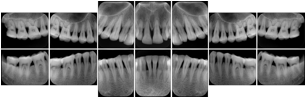

In most standard cases, images are oriented in structured layouts. These structured displays are useful to be shared between providers for reference purposes.

Table OO.1.1-1 shows structured display standard templates, where Viewset ID is based on the Japanese Society for Oral and Maxillofacial Radiology (JSOMR) classification provided by JIRA (Japan Medical Imaging and Radiological Systems Industries Association, www.jira-net.or.jp). Expected or typical teeth to be imaged location, region and designation codes are based on ISO 3950-2010, Dentistry - Designation system for teeth and areas of the oral cavity. For all the hanging protocols listed in OO.1.1-1, the value to use for Hanging Protocol Creator (0072,0008) is "JSOMR" and the value to use for Hanging Protocol Name (0072,0002) does not include "JSOMR" (e.g., "DL-S001A", not "JSOMR DL-S001A").